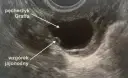

Głównym celem badania per rectum w gabinecie ginekologicznym jest ocena struktur anatomicznych, które są niedostępne lub trudne do zbadania w klasycznym badaniu ginekologicznym przez pochwę. Pozwala ono na precyzyjną ocenę takich elementów jak więzadła krzyżowo-maciczne, przegroda odbytniczo-pochwowa, tylna ściana macicy czy zagłębienie odbytniczo-maciczne (tzw. zatoka Douglasa). Właśnie w tych miejscach mogą rozwijać się patologie, które są kluczowe dla prawidłowej diagnozy.